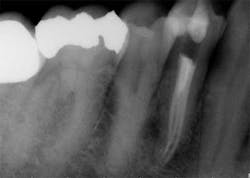

The success of endodontic treatment is directly related to the clinician’s ability to remove maximum numbers of bacteria from the root canal system. (1,2) If we can agree that all root canal treatment is associated with a certain degree of skill and precision in spite of perceived ease of treatment, I think it is fair to say there are no easy root canals. Some teeth are more difficult than others due to access limitations or anatomy, but the problem that faces all of us, in every tooth, is our inability to measure the absence of bacteria within the root canal and the potential for microanatomy to exist at any level of the root—whether it is a five-canal molar or a single-rooted anterior. It is impossible to determine the exact terminus of the root canal system, and there is no uniform agreement about where the root canal system ends. (3,4) The use of an apex locator can aid in this determination, but there is often disagreement between radiographic information and an apex locator, even in single-rooted anterior teeth, because the canal terminus can be at the radiographic apex or as much as 3 mm from it. (5) All instrumentation techniques leave a certain amount of the canal wall untouched, and we are not able to sterilize the root canal system. (6,7) The apical portion of any tooth may have dentinal tubules that can harbor bacteria, and the concept of a single uniform canal opening at the apex is anything but accurate. (8,9) Many teeth will have multiple portals of exit that may or may not be present in the apical third of the root. (Figure 1) As a result, the clinician must assume the apical canal anatomy in every tooth is highly variable in size, shape, and number (10,11,12) and there are no “easy ones.”

maxillary central incisor with a necrotic pulp. A prominent lateral canal can be seen,

but there is no way to know if multiple microscopic branches are present at any level

of the root canal system.